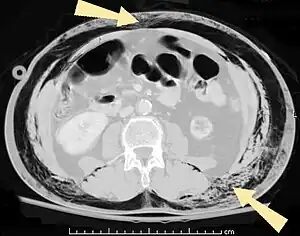

Significant cases of subcutaneous emphysema are easy to diagnose because of the characteristic signs of the condition.[1] In some cases, the signs are subtle, making diagnosis more difficult.[13] Medical imaging is used to diagnose the condition or confirm a diagnosis made using clinical signs. On a chest radiograph, subcutaneous emphysema may be seen as radiolucent striations in the pattern expected from the pectoralis major muscle group. Air in the subcutaneous tissues may interfere with radiography of the chest, potentially obscuring serious conditions such as pneumothorax.[18] It can also reduce the effectiveness of chest ultrasound.[27] On the other hand, since subcutaneous emphysema may become apparent in chest X-rays before a pneumothorax does, its presence may be used to infer that of the latter injury.[13] Subcutaneous emphysema can also be seen in CT scans, with the air pockets appearing as dark areas. CT scanning is so sensitive that it commonly makes it possible to find the exact spot from which air is entering the soft tissues.[13] In 1994, M.T. Macklin and C.C. Macklin published further insights into the pathophysiology of spontaneous Macklin's Syndrome occurring from a severe asthmatic attack.